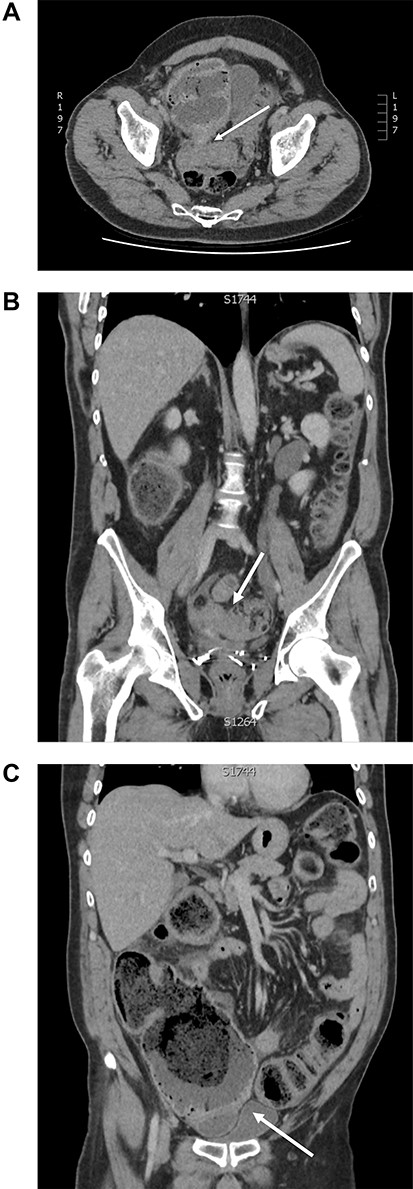

At the time of review, patient was febrile (39°C), tachycardic (110 bpm), with four quadrant peritonism and raised inflammatory markers. CT showed distended large bowel loops extending from caecum to a suspected transition point in distal sigmoid colon with pneumoperitoneum (Fig. 2). Emergency laparotomy was arranged for intraabdominal sepsis, presumably from large bowel perforation.

Computed tomography of large bowel obstruction and pneumoperitoneum: (A) axial view depicting dilated caecum with pneumatosis and adherence to the sigmoid stricture (white arrow); (B) coronal view depicting sigmoid stricture (white arrow); (C) coronal view depicting pneumoperitoneum, dilated caecum with adhesion to sigmoid colon stricture (white arrow).